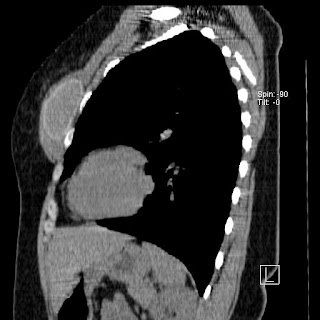

New CT images (without contrast) for 40 year old female with silicone breast implants. Formal diagnosis is expected soon. Images from 2010 can be seen here http://radiology-images.blogspot.com/p/40-year-old-female-silicone-implants.html